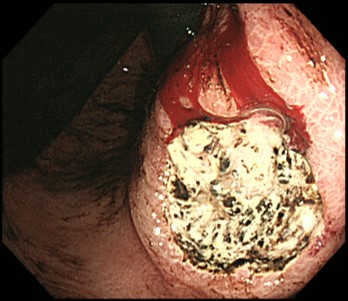

食道カンジダ症

カンジダは真菌(カビ)であり、常在菌です。通常は、感染することはありませんが免疫力が低下していると感染を起こし増殖します。そのため、糖尿病などの既往症がある場合や別の疾患でステロイド治療を受けている場合にはリスクが高いと言えます。感染して増殖すると食道粘膜で白い苔(こけ)のように広がり、胃カメラ検査で簡単に発見できます。つかえやしみる感じといった自覚症状はないこともあります。自然治癒が期待できる場合は経過観察し、症状がある場合には抗真菌薬の内服による治療をおすすめしています。

カンジダは真菌(カビ)であり、常在菌です。通常は、感染することはありませんが免疫力が低下していると感染を起こし増殖します。そのため、糖尿病などの既往症がある場合や別の疾患でステロイド治療を受けている場合にはリスクが高いと言えます。感染して増殖すると食道粘膜で白い苔(こけ)のように広がり、胃カメラ検査で簡単に発見できます。つかえやしみる感じといった自覚症状はないこともあります。自然治癒が期待できる場合は経過観察し、症状がある場合には抗真菌薬の内服による治療をおすすめしています。